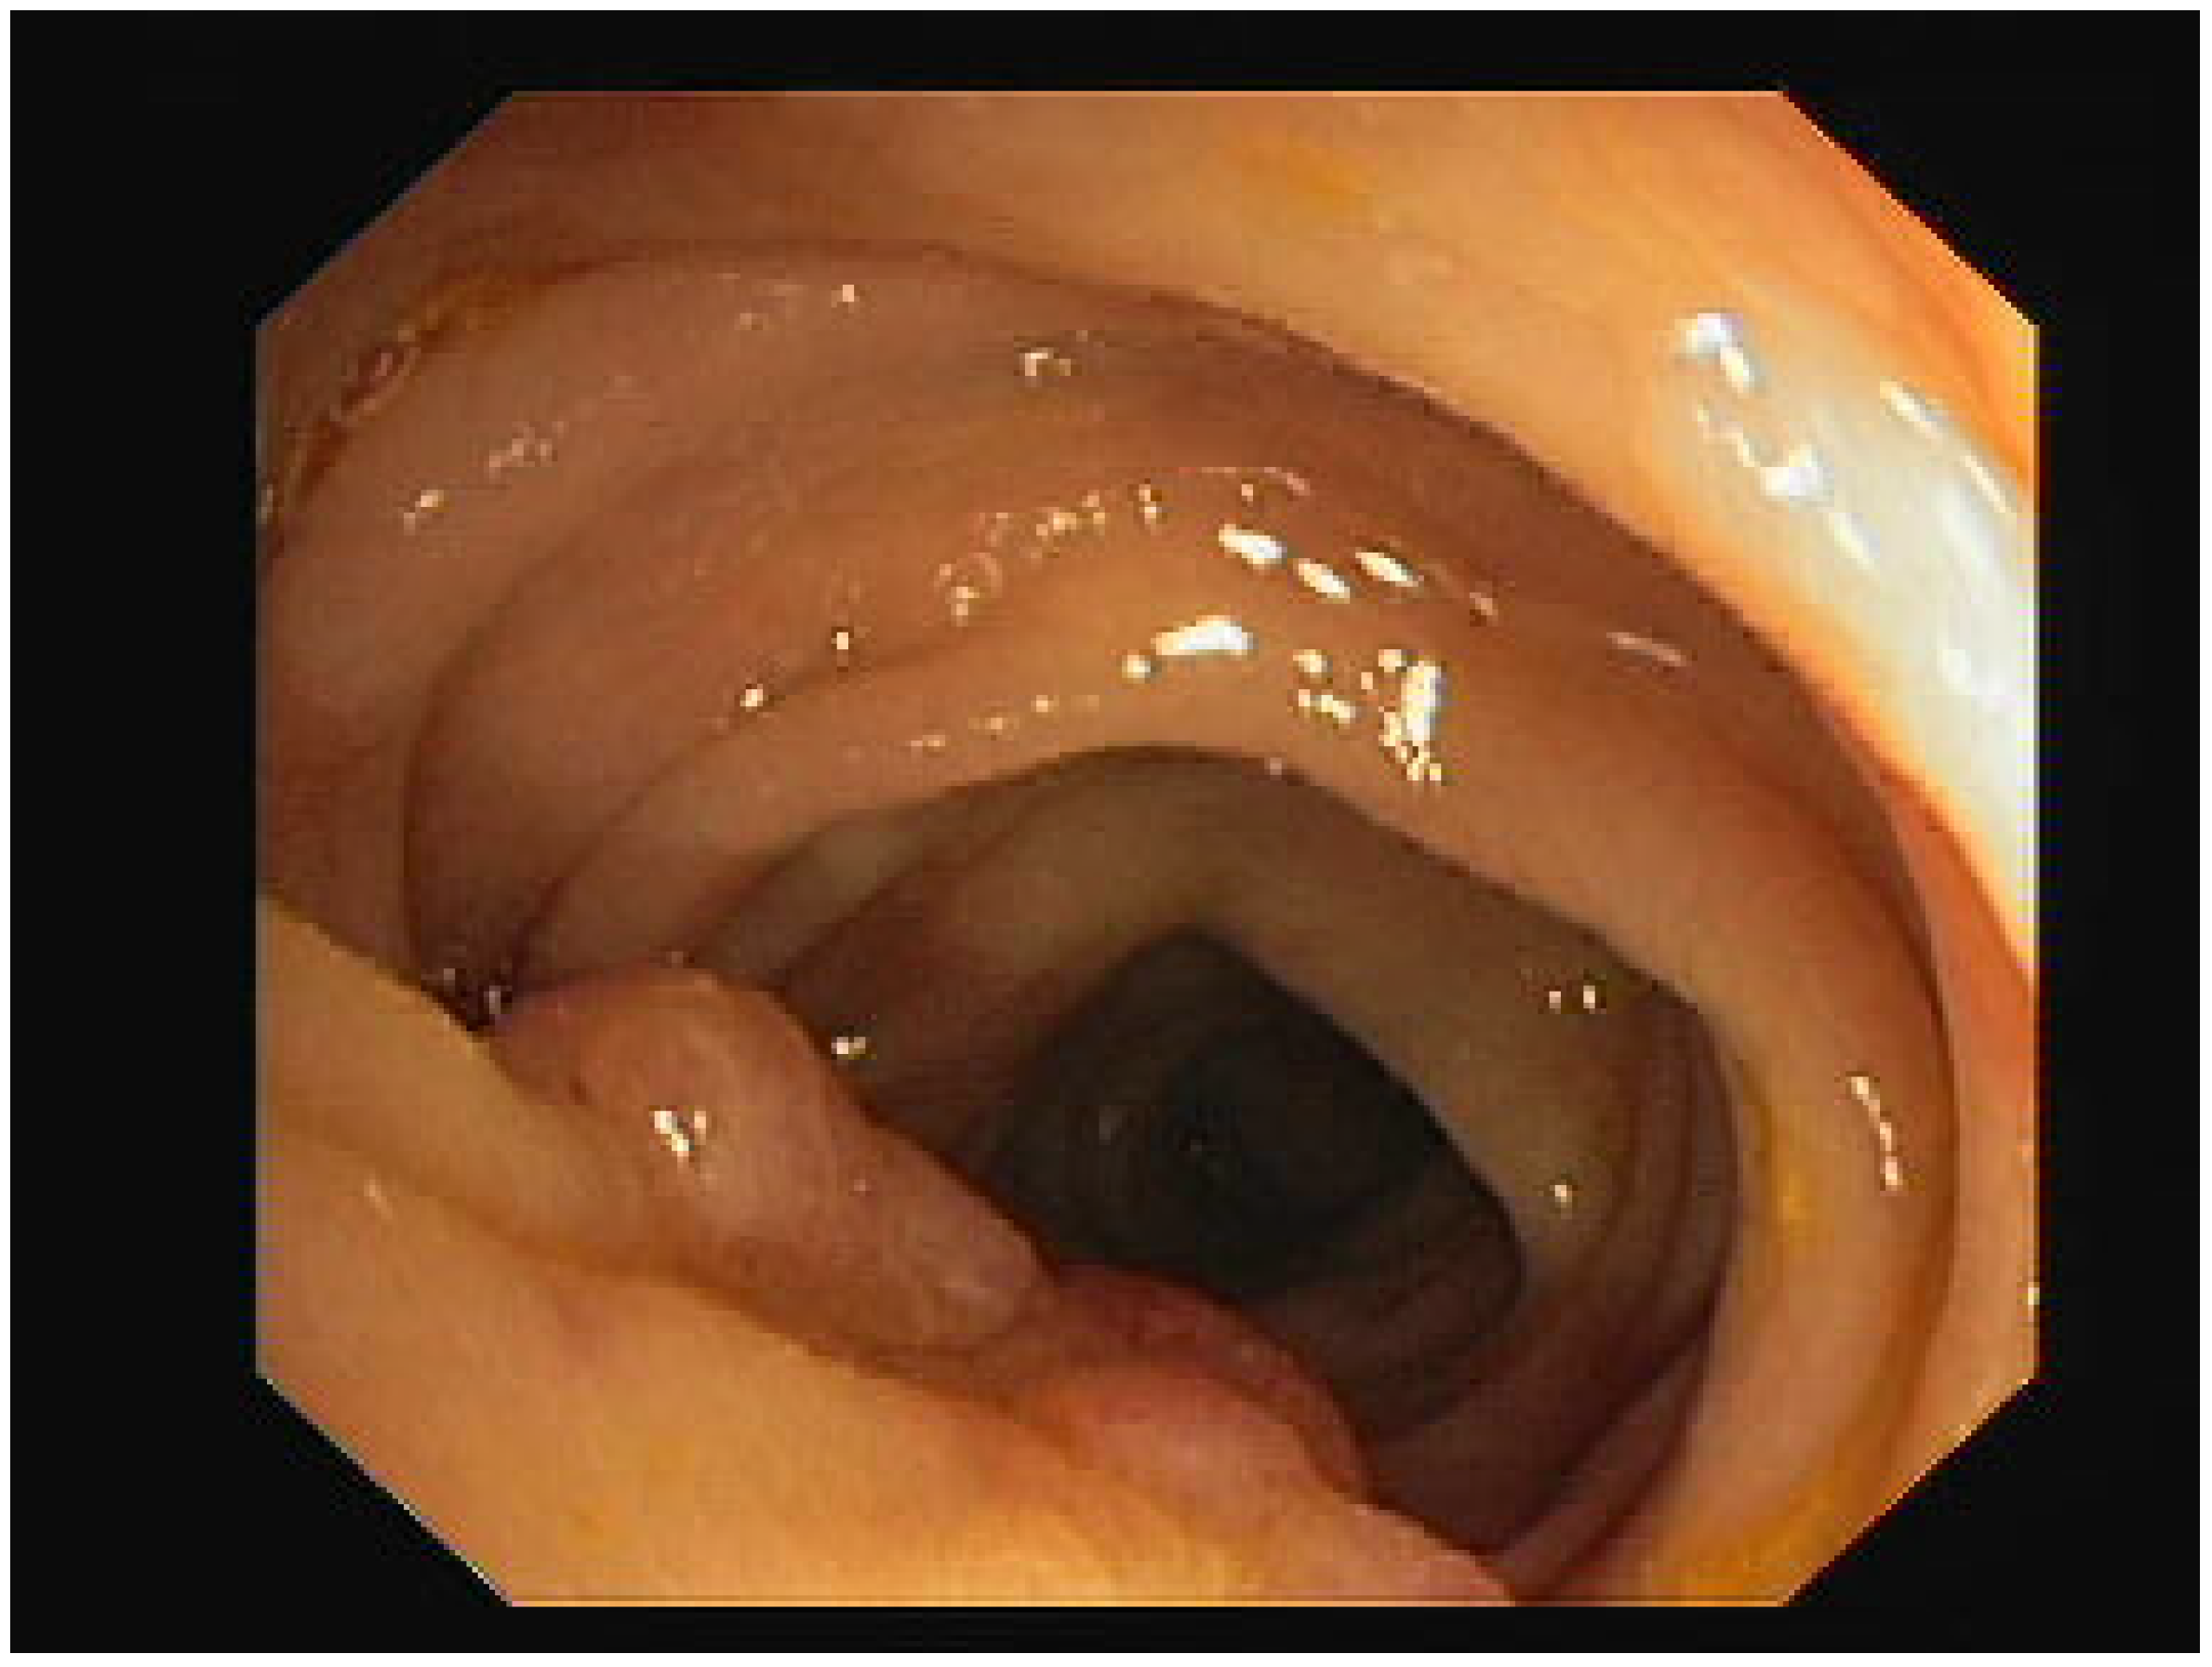

As an experiment, we focused on testing one type of the previously presented GAN methods on a dataset containing medical images. The name of the dataset is CVC-ClinicDB [28] and it is a dataset with 612 images with a resolution of 384 × 288, extracted from the video of a colonoscopy. The dataset was created by the Computer Vision Center, Barcelona, Spain, based on data from The Clinic Hospital of Barcelona. We chose to generate new enhanced resolution images, using different variations of the ESRGAN, with the purpose of finding out how the distribution of the image would differ. First, we generated an image with increased resolution, using the GAN, then, we resized the image to the original size, and finally, we plotted the distribution of the image in comparison to the original one. To do this, we plotted a histogram containing the frequency of the pixel values from 0 to 256.

For our experiments, we first used an ESRGAN. Compared to the original SRGAN, it contains a deep neural network that uses residual-in-residual dense blocks, instead of the batch normalization layers. The idea is to generate some new images with their resolution increased (1152 × 1536) and then resize them to the original dimension of the image (288 × 384). The objective is to obtain similar looking images, so that the discriminator is performing its role well, but we do not need the images to have exactly the same distributions, hence the goal is to obtain some new data. It can be seen in Figure 1 and Figure 2 that the distributions of the original image and the generated image are similar, but not identical.

Figure 1.

Original image histogram.

In Figure 1 and Figure 2, the image pixel distribution for the original image and the ESRGAN generated image can be observed.